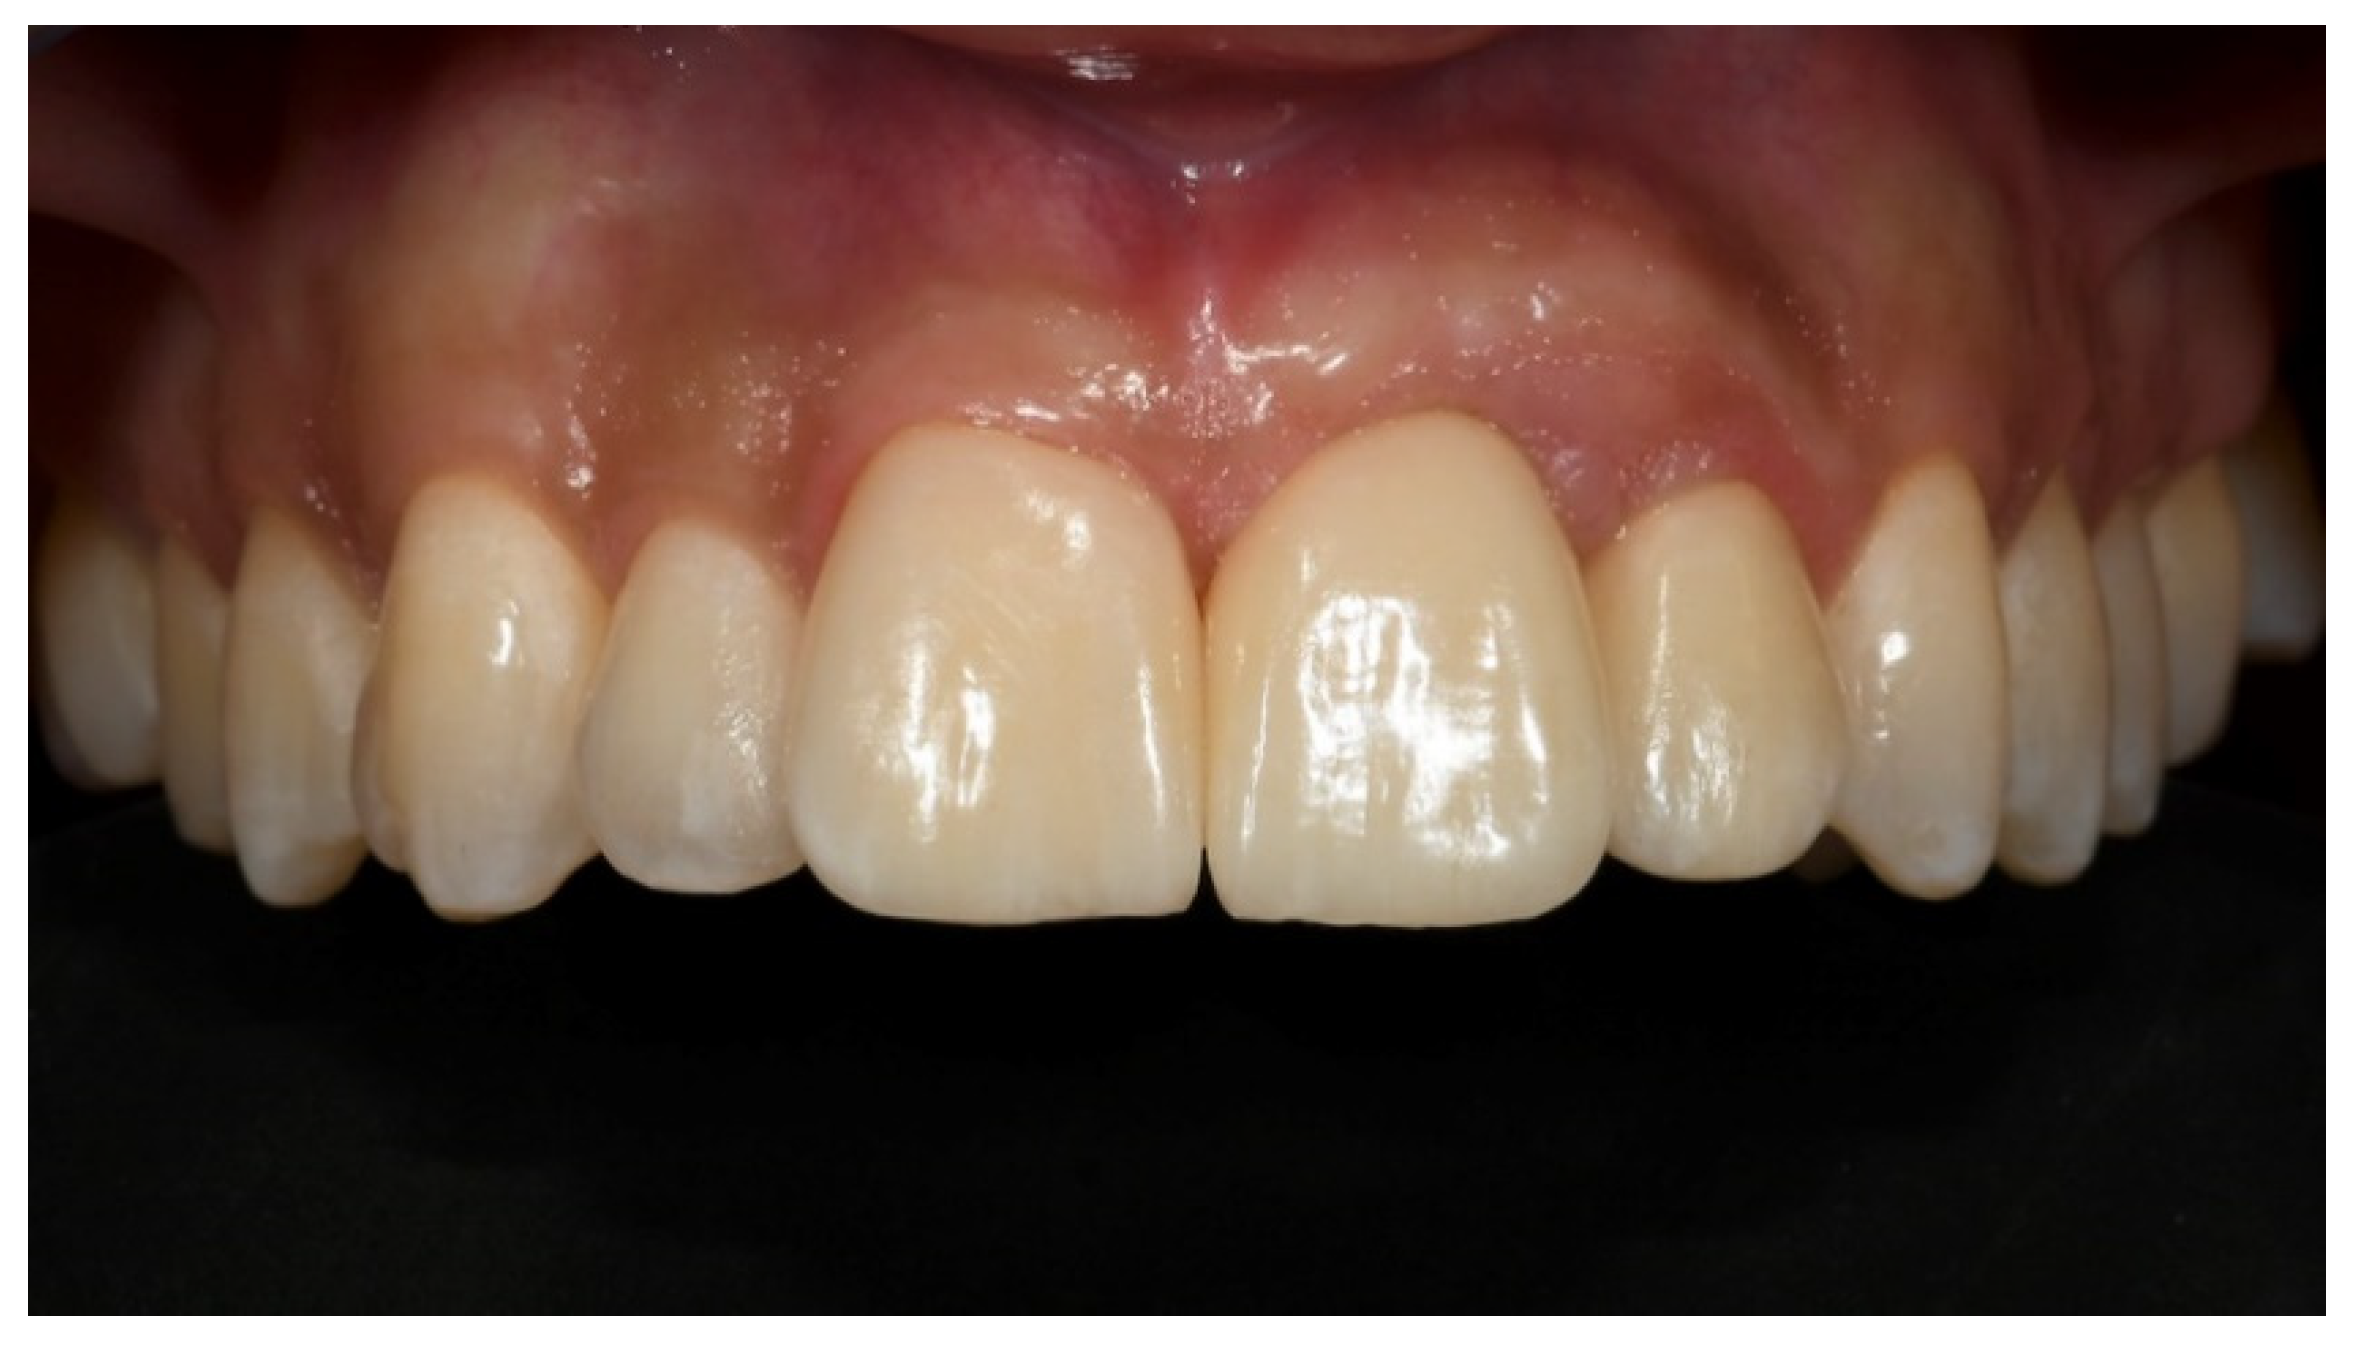

2. Case Presentation